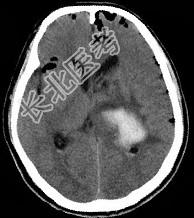

- 单项选择题男,32岁, 外伤后一天,CT检查如图, 下面何项诊断最恰当 ( )

A、脑出血

B、颅脑外伤

C、颅内积气

D、脑膜瘤

E、脑出血并颅内积气